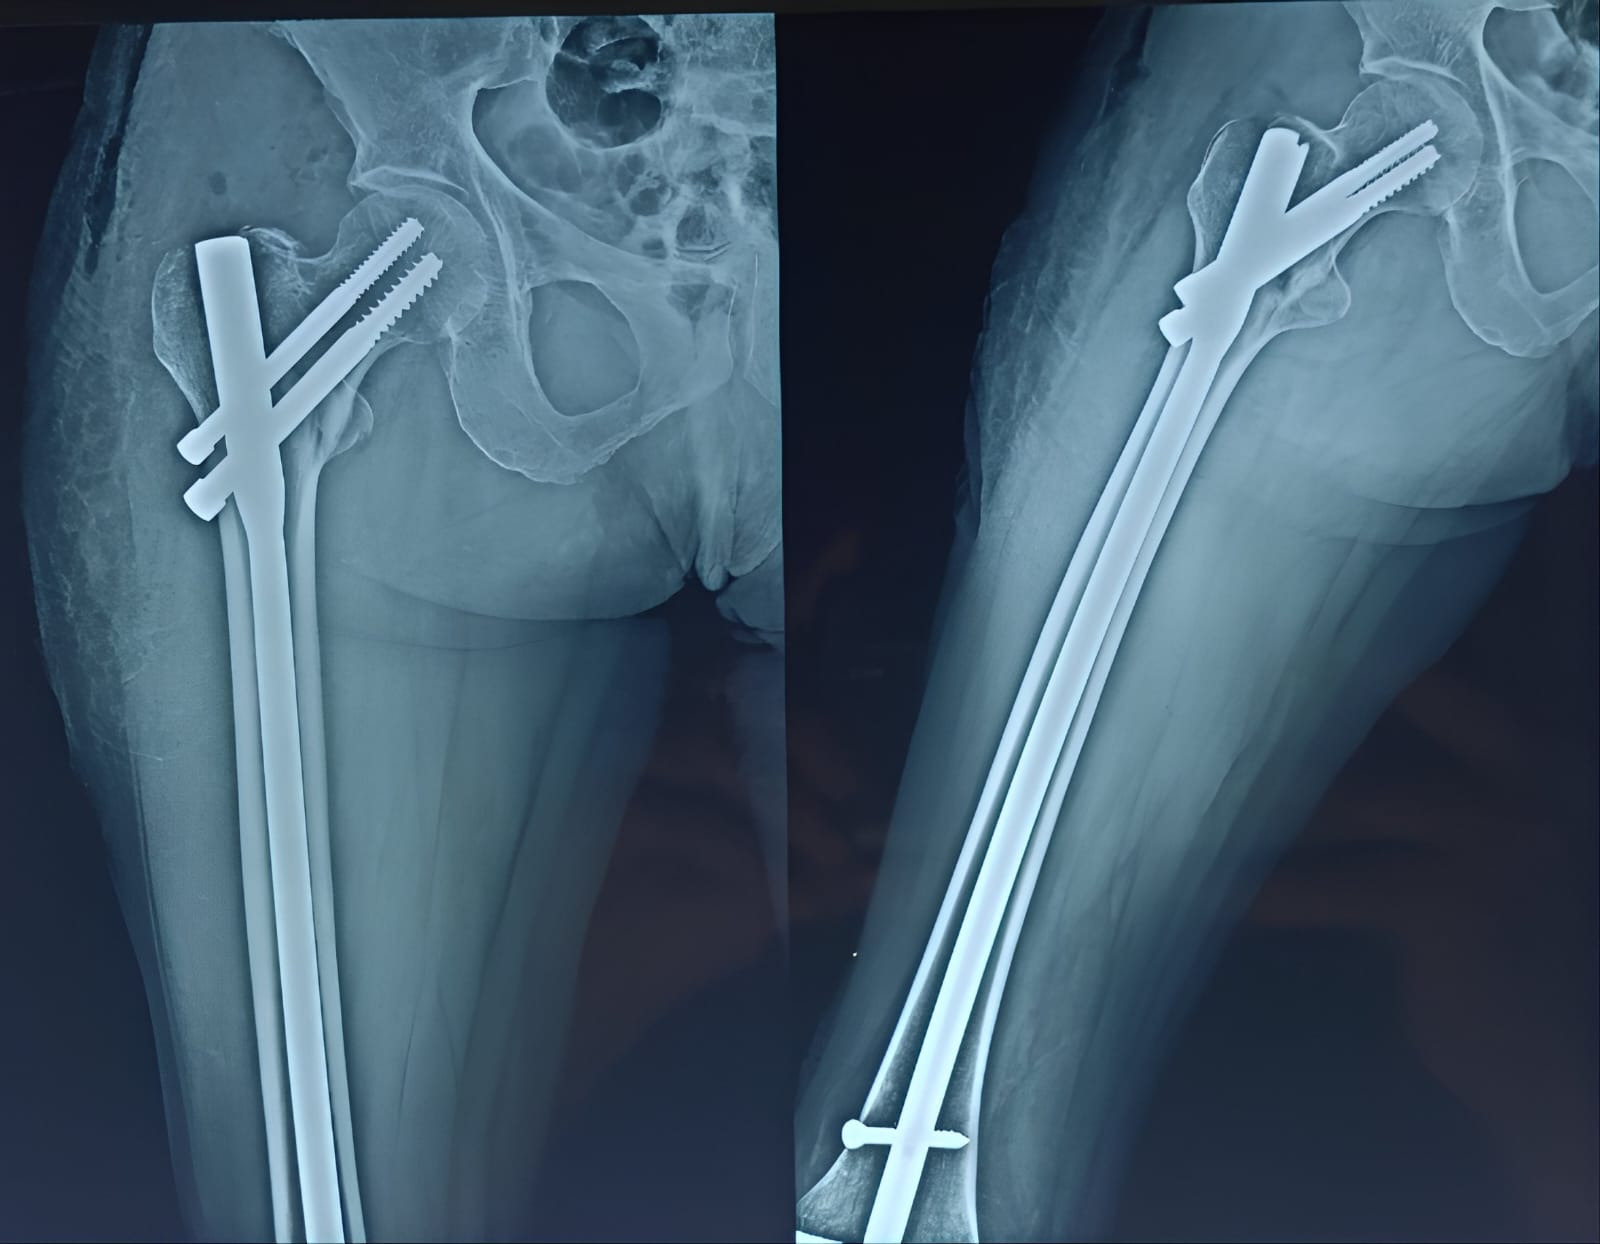

Fracture and Trauma Surgery

Gallery